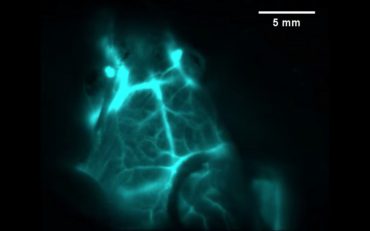

암종양을 비침습 관찰할 심부 이미징 기술

이석원 기자

2019년 12월 2일